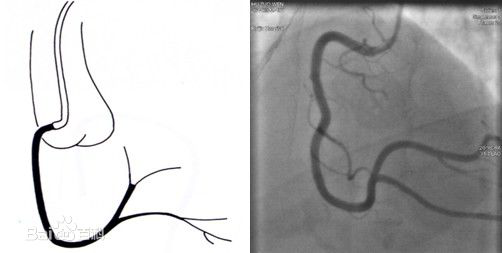

左前斜:RCA呈“C”型,观察RCA开口、起始部至后降支

-

后前位+头位:RCA呈“L”型,观察RCA远端分支及其开口情况